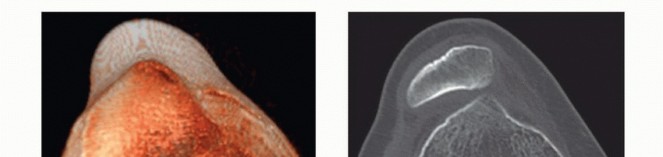

DEFINITION The term osteochondral lesion of the talus (OLT) refers to any pathology of the talar articular ca…